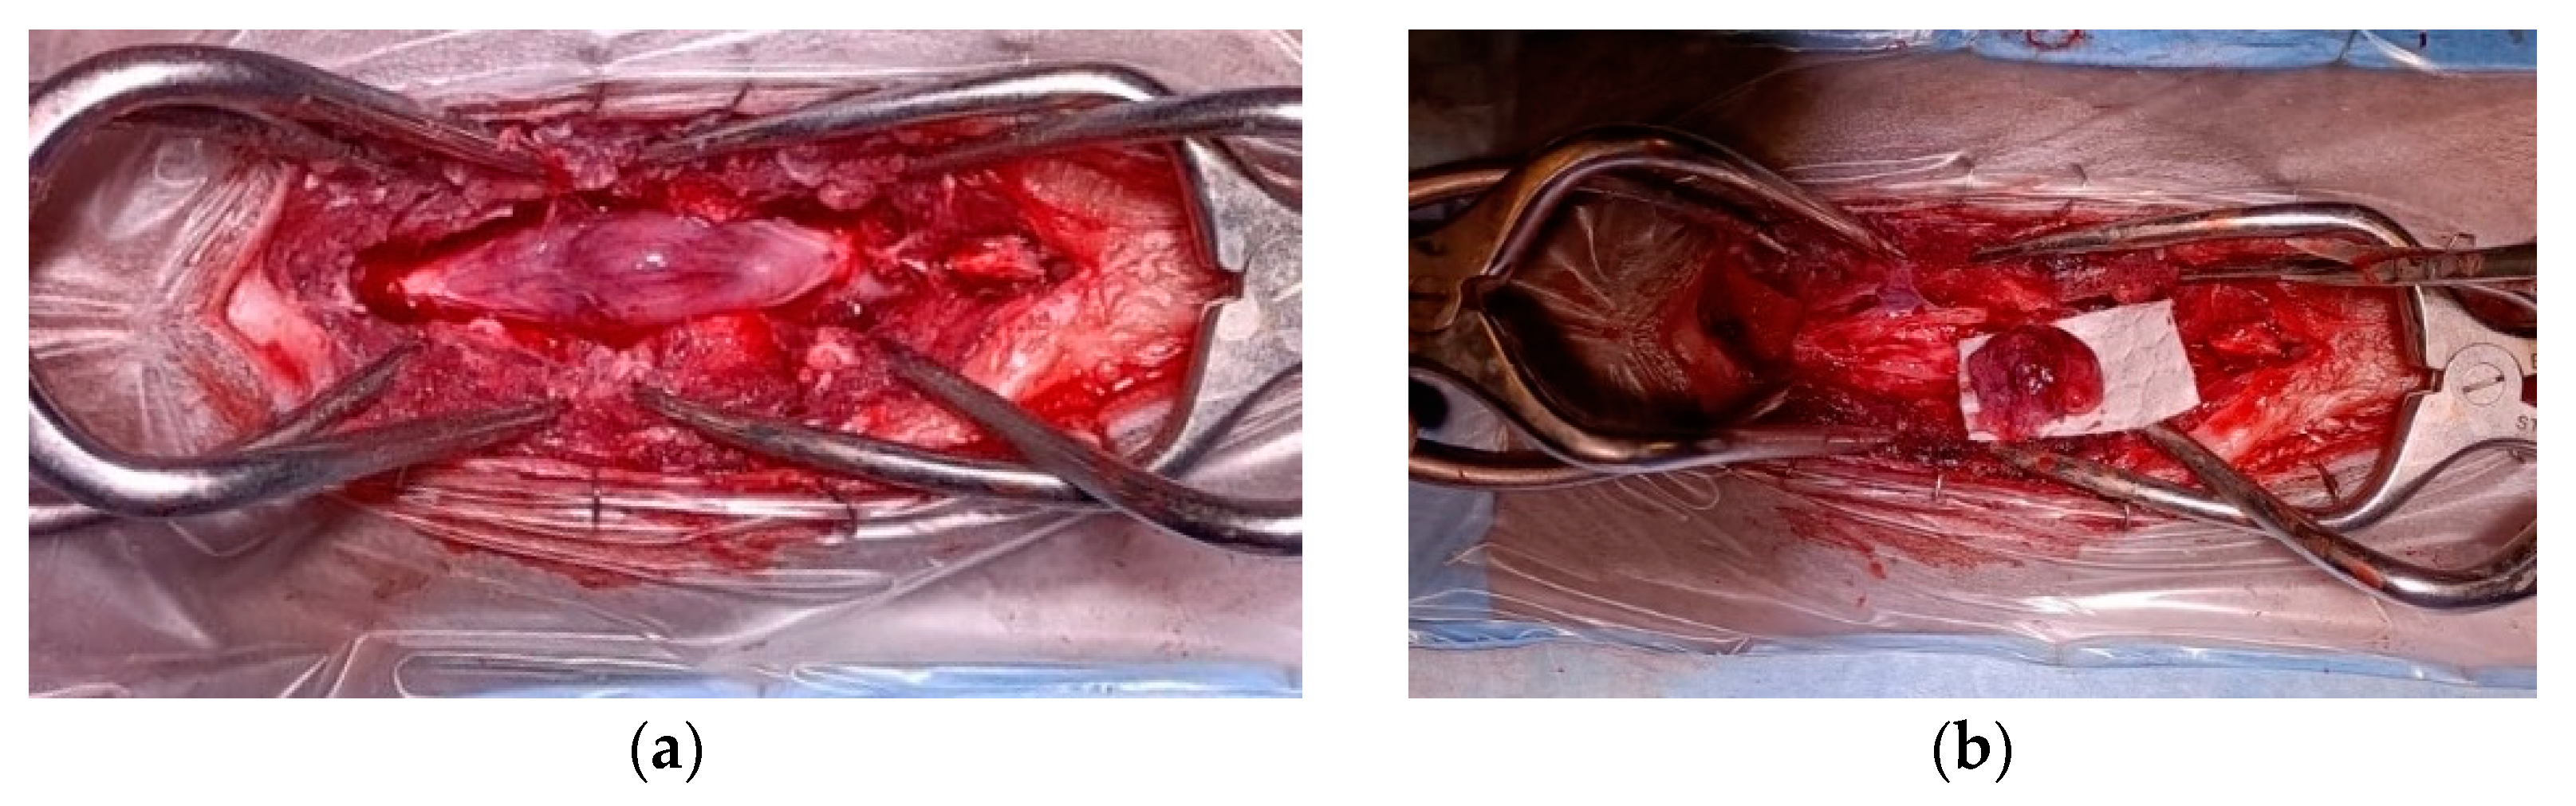

Grossly, the tumor had a gelatinous and reddish appearance and was adherent but easily separable from the dura mater and infiltrated the spinal cord parenchyma (Figure 2). Using a surgical microscope, the mass was meticulously and gently removed by detaching it from the dura mater and the spinal cord parenchyma. However, complete removal could not be assured due to the difficulty in distinguishing the margins between the neoplastic tissue and the edematous spinal cord parenchyma.

Figure 2.

Spinal cord medulloepithelioma in the cat. (a) After durotomy, the appearance of the intradural-extramedullary space-occupying mass extending from L5 to L6; (b) the medulloepithelioma after resection.